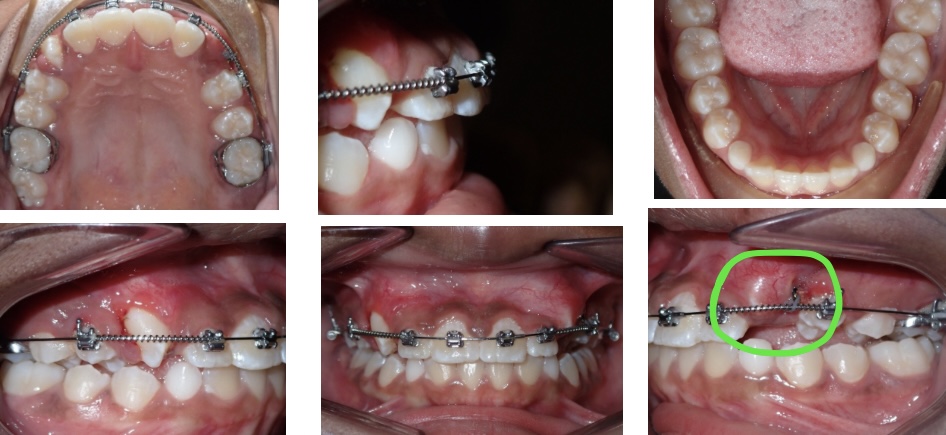

Solution. In Lauren’s case, in order to further bring the teeth into the best "spot," help was needed! We referred Lauren to an oral surgeon or periodontist who performs an "exposure" procedure.

The Process. During this procedure, Lauren’s mouth was numbed. The periodontist or oral surgeon makes his/her way through the gum tissue and bone and glues a small button on the tooth. The button is then attached to a short gold chain. Back at the orthodontist office, we attach this chain to the wire of Lauren’s braces. Over a series of visits, we slowly pull the teeth closer and closer until we can finally see them poke through the gum tissue! Take a look at the highlighted areas below to see the areas where we slowly encouraged Lauren’s teeth to the correct positions.